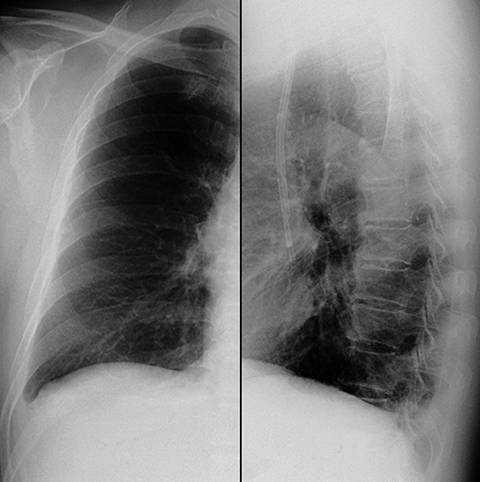

Pleural Effusion, Small to Moderate [3 of 5]